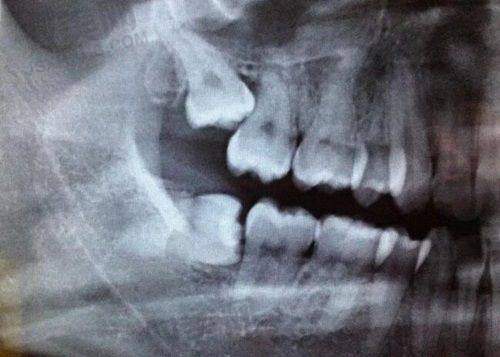

当虫吃牙处于浅龋阶段时,牙齿表面可能只是出现小黑点或小黑洞。此时治疗相对简单,通常采用补牙的方法。医生会先将龋坏的部分去除,然后用补牙材料进行填充。这样可以阻止龋坏进一步发展,修复牙齿的外形和功能。一般来说,补牙后牙齿可以正常使用,但要注意保持口腔卫生,避免再次发生龋坏。个体成效存在差异,有些人补牙后可能会有轻微不适,但通常会特别快缓解。

如果虫吃牙发展到中龋或深龋,细菌可能已经感染到牙髓,引起疼痛。这时可能需要进行根管治疗。根管治疗是先将感染的牙髓去除,然后对根管进行清理、消毒和填充。虽然过程相对复杂,但能有效解决疼痛问题,保留牙齿。治疗后,一般还需要做牙冠来保护牙齿。不过,根管治疗后的牙齿相对比较脆弱,使用时要格外小心。个体成效存在差异,部分人治疗后可能需要一段时间来适应。

龋坏牙早期,龋坏程度较轻,还未形成明显的龋洞时,可以采用药物治疗。医生会使用氟化物等药物涂抹在牙齿表面,增强牙齿的抗酸性,抑制细菌生长,从而终止龋坏的发展。这种治疗方法操作简单,患者痛苦小。但需要定期复查,观察龋坏的变化情况。个体成效存在差异,有些患者通过药物治疗能有效控制龋坏,而有些可能成效不太理想,还需进一步治疗。

当龋坏牙形成龋洞后,就需要进行充填治疗了。和虫吃牙的补牙类似,医生会先去除龋洞内的腐质,然后选择合适的充填材料进行填充。充填材料有多种,如树脂材料、玻璃离子材料等。不同的材料有不同的特点,医生会根据患者的具体情况进行选择。充填治疗后,要注意避免吃实力强的食物,防止充填材料脱落。个体成效存在差异,有些人充填后牙齿使用多年都没问题,而有些人可能会出现充填物松动等情况。